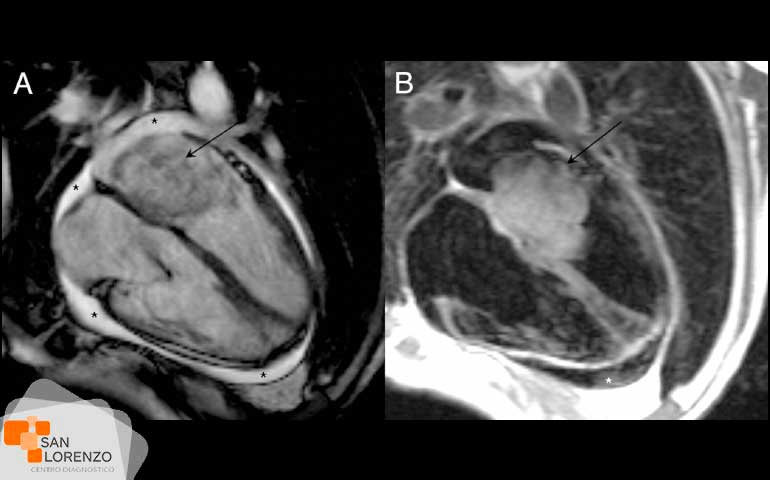

La resonancia magnética cardíaca (RMC) es una técnica de imagen para el estudio del corazón que utiliza ondas de radio potentes para crear imágenes de la estructura interna y alrededor del corazón a través de imágenes de alta resolución, y en centro de diagnóstico San Lorenzo, hacemos posible que en un solo examen podamos obtener información sobre la función y estructuras detalladas del corazón donde están incluidas las cavidades y las válvulas. Gracias a este tipo de examen hoy disponible en Rancagua y región de O’Higgins, podemos obtener imágenes en cualquier plano con alta calidad o definición de imagen, sin la necesidad de viajar a Santiago y con la posibilidad de realizarlo este procedimiento sin ningún tipo de contraste intravenoso.

La resonancia magnética cardíaca, se utiliza para que médicos tratantes puedan determinar la función de cardiopatías congénitas, anomalías de las coronarias, estudios del músculo cardiaco, estudios de función ventricular, estudios de las enfermedades del músculo cardiaco, de la capa de tejido que recubre corazón y masas cardiacas por mencionar algunos.

La tomografía computarizada y la resonancia magnética son técnicas de imágenes diferentes, que con los progresos tecnológicos tienen primer lugar en la evaluación cardíaca. La gran diferencia consiste en el uso de la radiación en el caso de TAC y en el uso de las ondas de radiofrecuencia en el caso de una resonancia magnética. El escáner o TAC cardíaco, es muy útil a para la evaluación de las finas y tortuosas coronarias dado que tiene una alta resolución espacial. En cambio, la resonancia magnética al corazón, tiene una alta resolución temporal y de contraste, por lo que es buena para la evaluación de función cardíaca y en la identificación de tejidos.

La resonancia magnética cardíaca se utiliza para determinar la función de cardiopatías congénitas, las anomalías de las coronarias, estudios del músculo cardiaco, estudios de función ventricular, estudios de las enfermedades del músculo cardiaco, de la capa de tejido que recubre corazón y masas cardíacas.